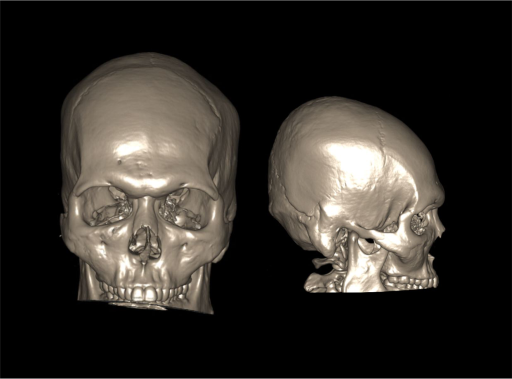

- 3d images to show fractures, dislocations or abnormalities.